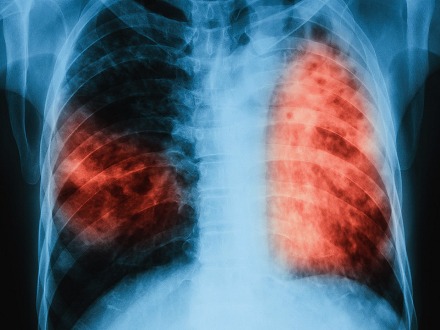

The Federal Government of Nigeria has intensified efforts to eradicate tuberculosis (TB) and other infectious diseases by adopting advanced technology and approving $54 million for the procurement of life-saving drugs, particularly for TB and HIV treatment.

As part of the National Strategic Plan for TB (2021–2026), Nzelu said the ministry is deploying innovative technologies to eliminate TB as a public health threat.